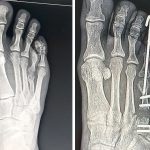

O Hospital Carlos Fernando Malzoni (HCFM) registrou um marco inédito em sua história recente ao realizar, no final de dezembro de 2025, uma cirurgia de braquimetatarsia, procedimento raro e de alta complexidade dentro da ortopedia especializada em pé e tornozelo, executado por meio de técnica percutânea, considerada menos invasiva em relação aos métodos tradicionais.

A braquimetatarsia é uma malformação congênita caracterizada pelo encurtamento anormal de um dos ossos do antepé, geralmente o quarto metatarso, condição que pode causar dor, alterações na marcha, dificuldade no uso de calçados e impacto estético significativo.

O que torna o caso ainda mais singular é a forma como a cirurgia teve início, como explica o Dr. Lucas: “Durante uma aula para a turma dos alunos do 6º ano da Faculdade, a Letícia me mostrou o seu pé com um quadro de braquimetatarsia, e me perguntou se eu saberia tratar. Me relatou que já havia visitado diversos ortopedistas, sendo que nenhum tinha experiência prévia com tal tipo de cirurgia para correção do quadro. Respondi a ela que a Braquimetatarsia é extremamente rara, porém eu já havia realizada tal correção previamente, e que poderíamos resolver o seu caso. Imediatamente solicitei as radiografias no ambulatório do hospital e já iniciamos a nossa programação cirúrgica, com todo o apoio do HCFM”.

No Brasil, a cirurgia de braquimetatarsia está concentrada em poucos centros de referência, geralmente ligados a hospitais universitários e grandes capitais, especialmente São Paulo. Além de rara, a técnica percutânea aplicada ao procedimento é ainda menos difundida, o que reforça o caráter altamente especializado da cirurgia realizada no HCFM. A realização do procedimento em Matão representa não apenas um avanço técnico, mas também um passo importante na interiorização da medicina de alta complexidade.

Letícia destaca que o processo ainda está em andamento, uma vez que o tratamento envolve o alongamento ósseo gradual, etapa que exige acompanhamento rigoroso. “Ainda estou na fase de alongamento ósseo, que é um processo lento e que exige paciência. Mas cada evolução representa uma melhora significativa, tanto do ponto de vista funcional quanto estético”, afirma.